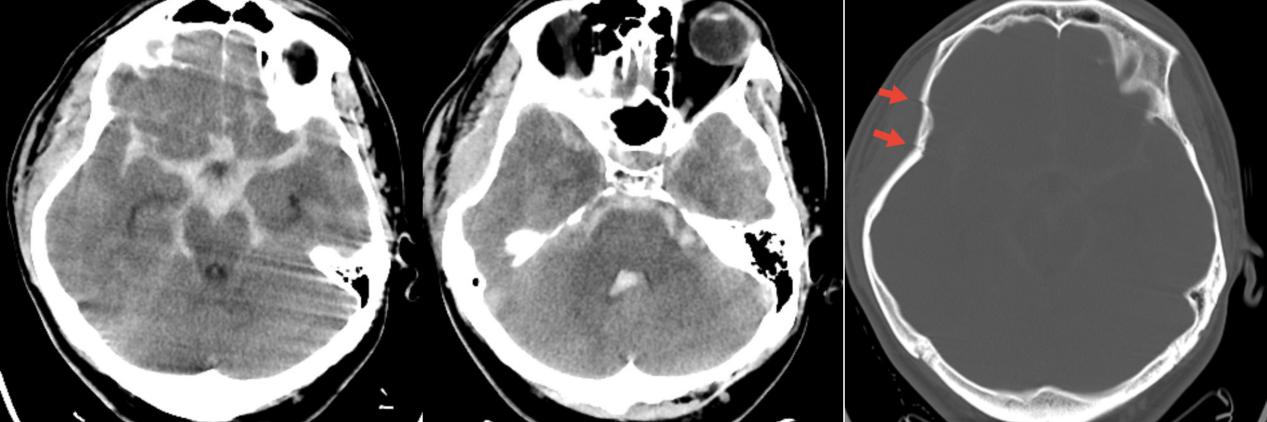

今年26岁的于先生,5月11日晚间被路人发现昏迷倒于路边,由救护车送至清华大学附属垂杨柳医院急诊科。当时无家属在场,病史不详。查体患者呈中度昏迷,GCS5分,右侧颞部头皮挫伤伴出血。双侧瞳孔直径3mm,对光反射消失。急查头颅CT显示广泛蛛网膜下腔出血,第三、四脑室积血,右侧颞骨凹陷骨折。

▲头颅CT显示广泛蛛网膜下腔出血,脑室积血,右侧颞骨凹陷骨折